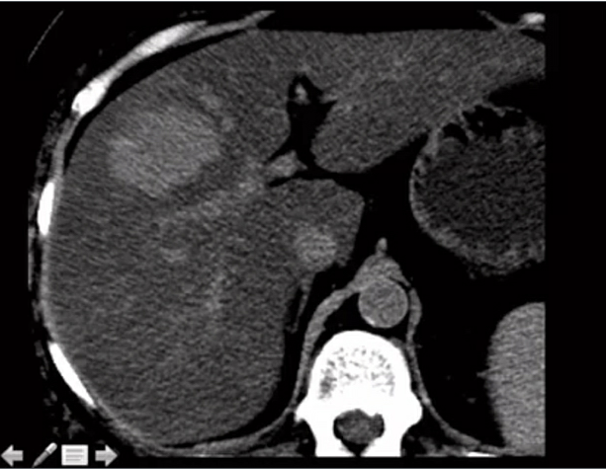

CT tech calls you to the scanner to console a pt who the tech just told has a horrible liver cancer. What is your next step?

get delayed images (10-20 min). this is most likely a cavernous hemangioma